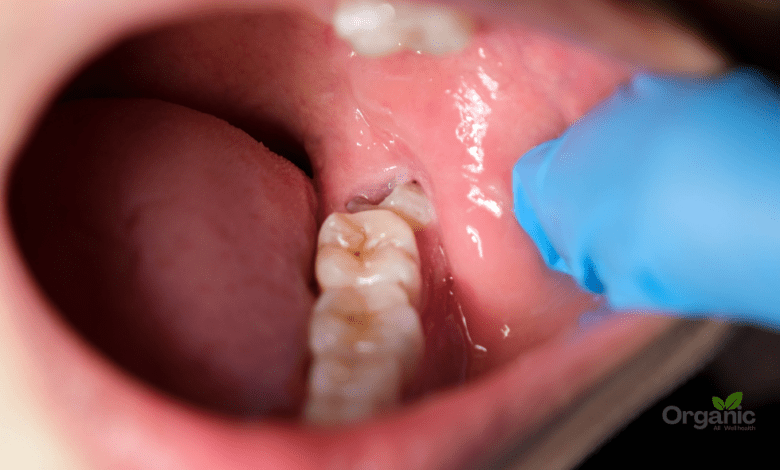

Impacted Wisdom Teeth क्या हैं?

जब अक्ल दाढ़:

- मसूड़े से पूरी तरह बाहर न आए,

- हड्डी में फंसी रहे,

- पास के दांत से टकरा जाए,

- या तिरछे एंगल पर बढ़े,

तो उसे Impacted Wisdom teeth कहा जाता है।

1. संक्रमण (Infection) और Pericoronitis

जब दाढ़ आंशिक रूप से निकलती है, तो उसके ऊपर मसूड़े का एक हिस्सा रह जाता है। वहां:

- खाना फंस जाता है

- बैक्टीरिया पनपते हैं

- सूजन, दर्द और बदबू पैदा होती है

इस स्थिति को Pericoronitis कहा जाता है।